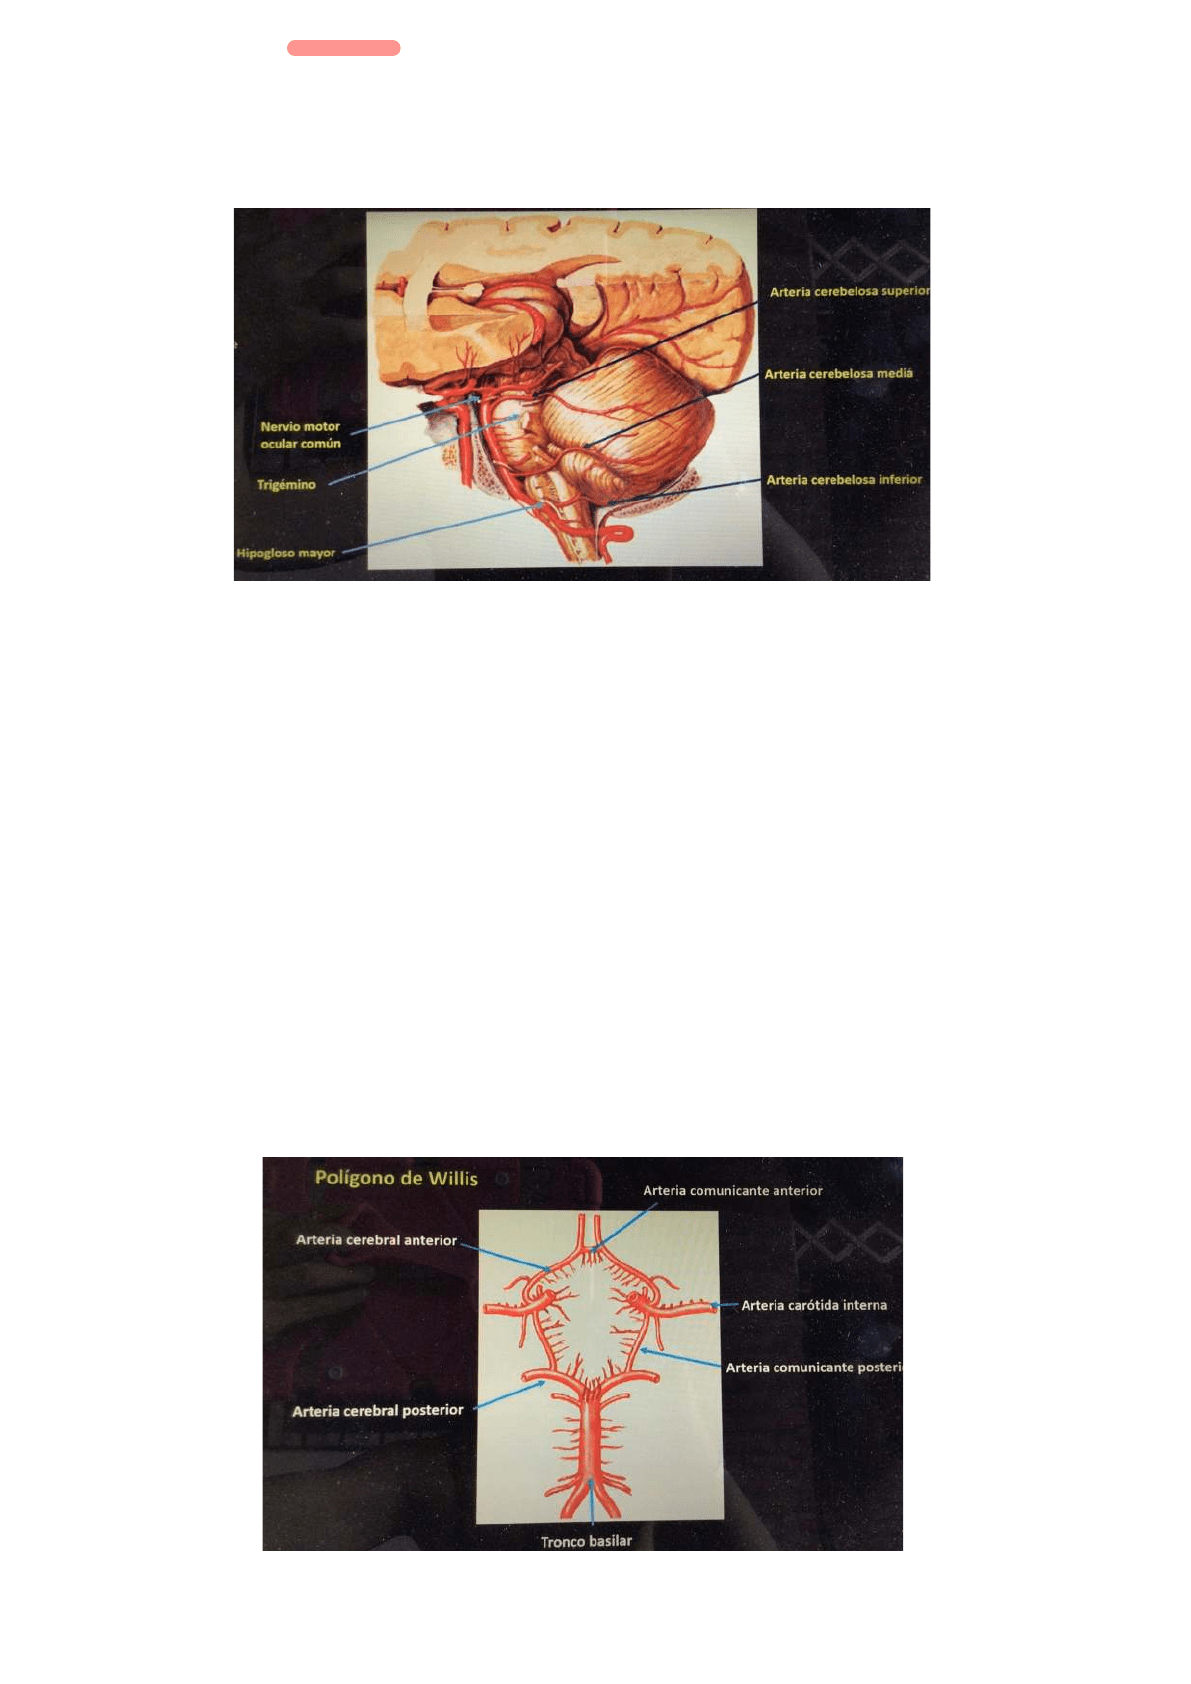

Antes de dar esas ramas dan muchas ramas colaterales para el bulbo, la protuberancia, los pedúnculos y el cerebelo. Son tres para cada uno.

Un primer grupo son las arterias paramediales: arterias que nacen directamente de la arteria vertebral y del tronco basilar

Las primeras se dividen en pequeños grupos que van al bulbo.

Arterias ponticas: destinadas a la protuberancia, nacen de la cara posterior del tronco basilar

Arterias de los pedunculos: cuando está terminando el tronco basilar

El siguiente grupo es el de las arterias cortas: Nacen de las partes laterales del tronco basilar, se distribuyen en bulbares, protuberanciales y pedunculares.

Un ultimo grupo lo constituyen las arterias largas: las tres arterias cerebelosas que vascularizan parte del tronco encefalico. Una es la arteria cerebelosa

inferior, colateral de la arteria vertebral en su porción terminal, ni bien nace se relaciona con el nervio hipogloso mayor (XII). La otra es la arteria

cerebelosa media que se origina en la parte media del tronco basilar, se relaciona con la emergencia del trigémino (V). La ultima es la arteria cerebelosa

superior que nace en la terminación del tronco basilar y bien nace se relaciona con el nervio motor ocular comun (VI), luego contornea el pedúnculo

superior, se distribuye por el vermis superior.

Polígono de Willis

Adelante las dos arterias carótidas internas

Atrás el tronco basilar

Las carotidas internas dan origen a las arterias cerebrales anteriores izquierda y derecha

El tronco basilar da origen a las dos arterias cerebrales posteriores derecha e izquierda

El circulo se cierra con las arterias comunicantes: una es anterior que comunica las dos arterias cerebrales anteriores y dos son posteriores que

comunican el sistema carotídeo con el tronco basilar.

LADOS

Hacia atrás por la bifurcación del tronco basilar con las arterias cerebrales posteriores hasta la implantación de las comunicantes posteriores a los lados.

A las comunicantes posteriores se les une las carótidas internas y adelante las cerebrales anteriores unidas por la comunicante anterior.

Ubicación

Espacio subaracnoideo de la base del cráneo

Hacia adelante es la cisterna quiasmática y hacia atrás se denomina cisterna protuberancial.

Hacia los lados esta el quiasma ópticos y hacia atrás y lateralmente los tuberculos mamilares y el hipotálamo.